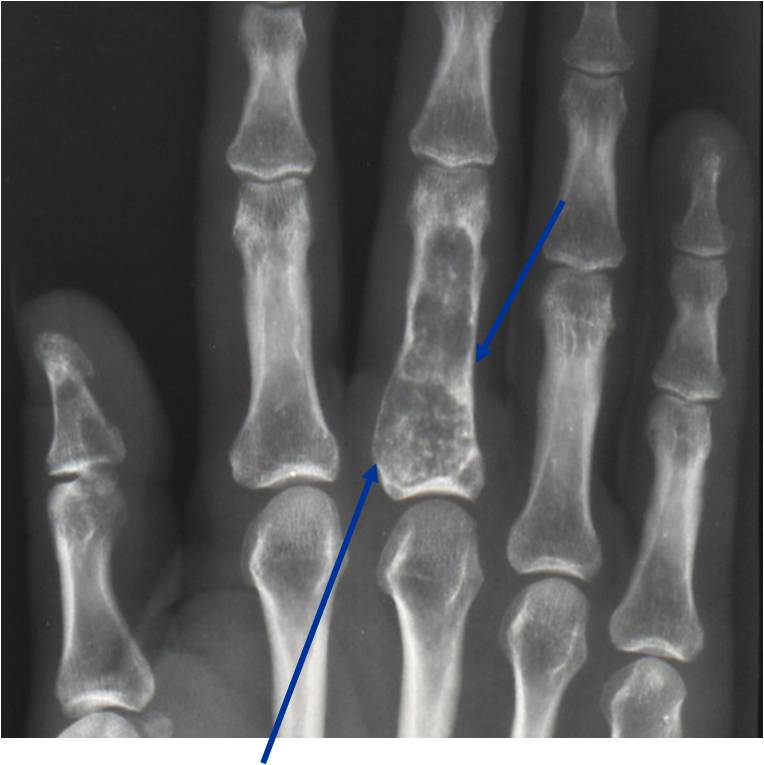

- Localized, radiolucent defect usually with punctate calcifications

- Calcifications are typical but not always present

- Matrix may demonstrate various degrees of calcification

- Calcifications are stippled, punctate, popcorn like calcifications and “Ring and Arc” calcifications

- Cartilage tumors grow in a lobular manner. The perimeters of the lobules undergo

- enchondral ossification that may calcify. If the entire perimeter of the lobule calcifies it appears

- radiographically as a “Ring”. If a portion of the perimeter of a lobule calcifies it forms an “Arc” on

- an X-ray.

Ring and Arc Calcifications, Minimal Endosteal Scalloping, Cortex Intact, No Soft Tissue Component, No Periosteal Reaction

Minimal Endosteal Scalloping is Acceptable

Metaphyseal Tumor, Heavy Calcifications, Ring and Arc Pattern of Calcifications, Minimal Endosteal Scalloping, No Cortical Destruction, No Periosteal Reaction, No Cortical Destruction, No Soft Tissue Component

Metaphyseal Tumor, Heavy Calcifications, Ring and Arc Pattern of Calcifications, Minimal Endosteal Scalloping, No Cortical Destruction, No Periosteal Reaction, No Soft Tissue Component